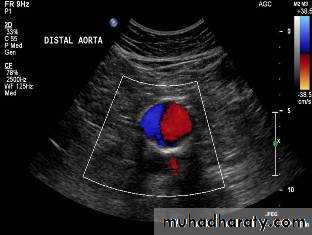

• Ultrasonography• Duplex ultrasound

Ultrasound & Duplex Ultrasound: